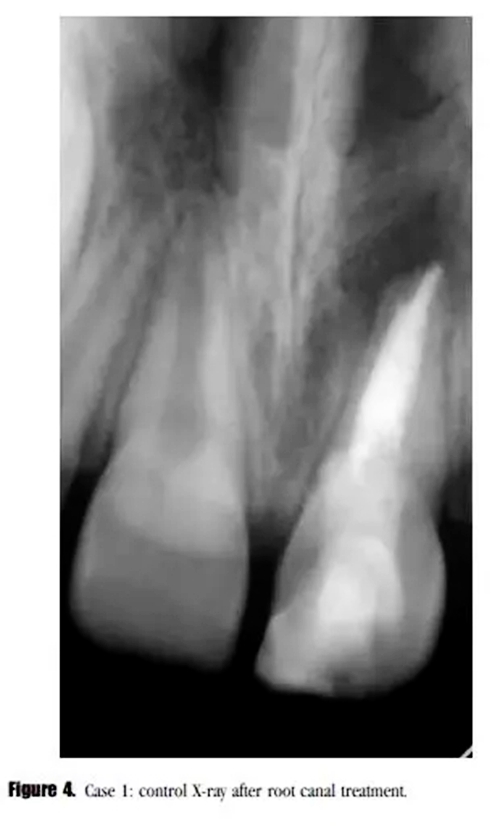

診斷為治療后的牙髓疾病復(fù)發(fā)。與患者家長(zhǎng)商談,1個(gè)月后進(jìn)行常規(guī)根管治療。根管內(nèi)使用 Total Fill RRM ( FKG Dentaire SA , La Chaux-de-Fonds , Switzeland )進(jìn)行單尖充填(圖4)。

在3個(gè)月后的回訪中,患者癥狀消失,X線顯示根尖透射區(qū)域減小。(圖5)